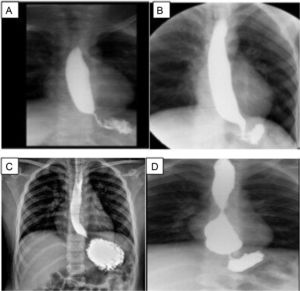

Manometría esofágica de los pacientes con obstrucción en el tracto de salida de la unión esofagogástrica (UEG).

Pacientes con historia de disfagia posfunduplicatura. La manometría de alta resolución fue consistente con obstrucción al flujo del tracto de salida de la UEG. La presión de relajación media fue de 24 mmHg, la peristalsis fue normal en todos los casos.

Todos ellos presentaron disfagia posterior al procedimiento quirúrgico con una media de dos semanas (2 ± 1.2 semanas). Por esta razón se les practicó, como primera prueba diagnóstica, un esofagograma, encontrando en los cuatro casos estenosis de la unión esofagogástrica (UEG) (fig. A-D 2). Posterior a esto fueron sometidos a endoscopía, encontrándose dificultad para el paso del endoscopio en dos de los casos, en uno se encontró angulación de la UEG, en el otro la endoscopia se reportó como normal.

Esofagograma de los pacientes posterior a funduplicatura.

A) Caso 1, sobredistensión de la luz esofágica al paso del bario. La unión esofagogástrica (UEG) se observa por debajo del diafragma; B) Caso 2, estrechez de la de la UEG; C) Caso 3, el esófago sobredistiende discretamente en sus tres tercios, con adelgazamiento de la unión esofagogástrica; D) Caso 4, esófago de calibre conservado en los dos primeros tercios, pero con gran aumento de su calibre en el tercio distal, punta roma e incluso con imagen redondeada, y reducción de calibre en la UEG, probable sobreeficiencia de la funduplicatura.